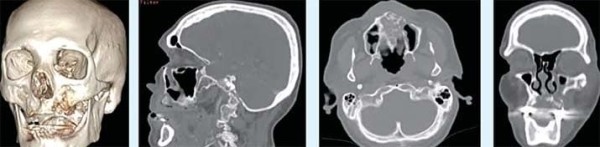

• Постковидные остеонекрозы костей лицевого отдела черепа